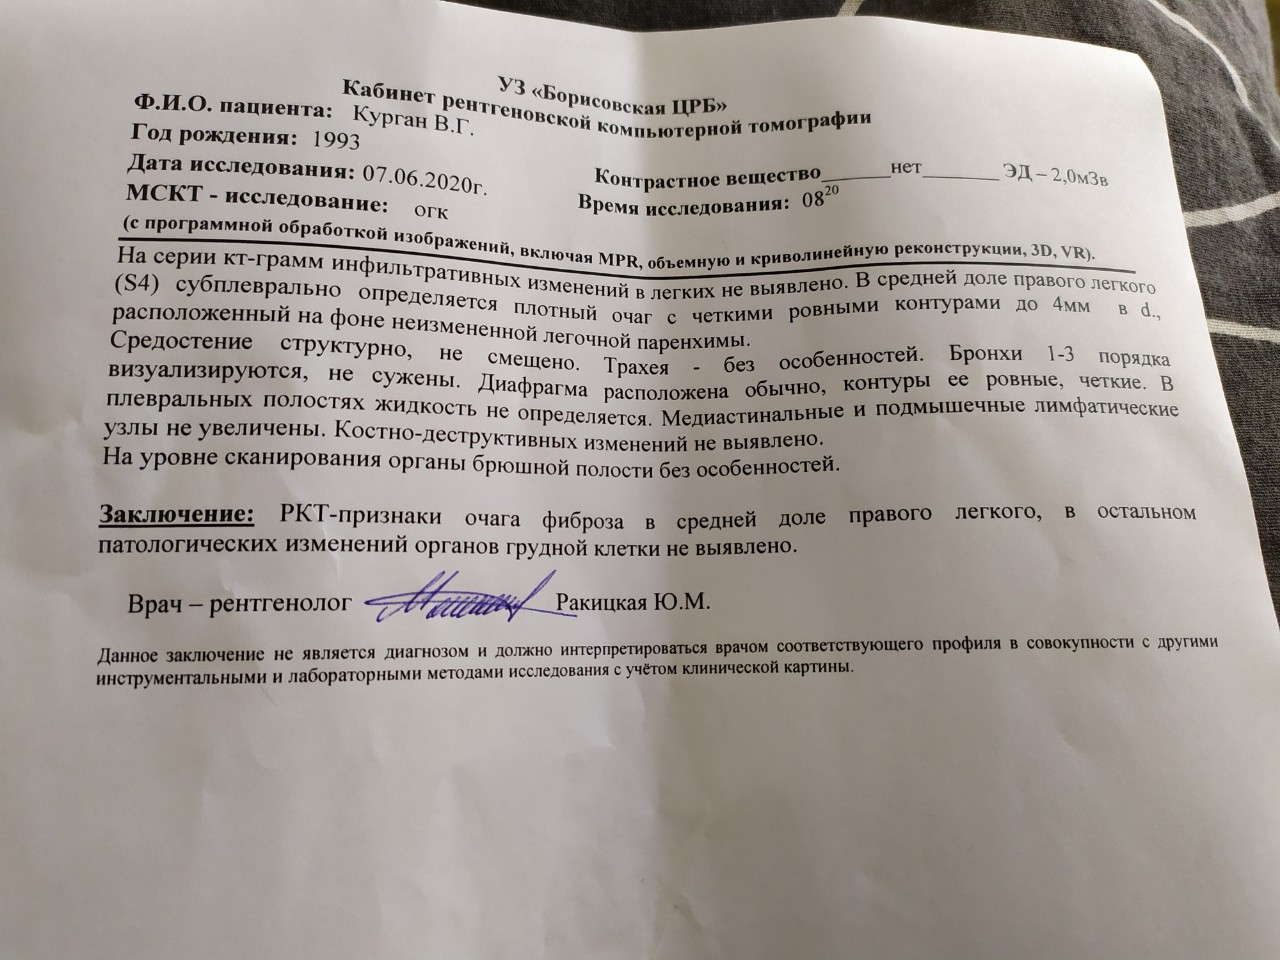

Фотографии и снимки КТ легких без контрастных веществ

Раздел: Визуальный дайджест